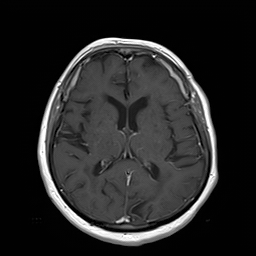

III-A Data

We analyze the performance of the proposed approach based on 21 pairs of clinical patient head datasets. First, 8 pairs of tomographic T1 and T2 Flair MRI datasets (256x 256256x256256\;\text{x}\;256) are used. Second, cone-beam X-ray and MRI projection images (512x 512512x512512\;\text{x}\;512) generated from 13 patients are utilized (MR: 1.5 T MAGNETOM Aera / CT: SOMATON Definition, Siemens Healthineers, Erlangen / Forchheim, Germany). Two pairs of patient dataset of each modality were reserved for validation and testing. Image registration of the corresponding datasets is performed using 3D Slicer [30]. The forward projections are based on the work of hybrid MR/X-ray imaging by [31, 32, 33] and are created with the CONRAD framework [34]. 108 projections are created per patient that are distributed equiangularly along the azimuthal and in 60 degree range along the inclination angle. Note that the type of data presented here is only to be seen as an example. The proposed approach is not tailored to any particular data type or combination of data types.

For the task of super resolution, low-resolution images are created by nearest neighbor downsampling by a factor of 4. For denoising, noisy images are generated from the ground truth by applying Poisson noise. Both methods are only an approximation of the real physical processes. In MRI, for example, the resolution and the signal-to-noise ratio are directly related [35]. Also, noise in X-ray imaging is not just Poisson noise but a combination of multiple sources of noise [36]. For detailed investigations on a specific problem area a corresponding simulation should therefore be conducted.

Figure 2: Inputs and outputs of the guided filtering pipeline based on the WDSR network. T1 & T2 MRI pairs (a)-(e) and CT & MRI projection images (f)-(j).